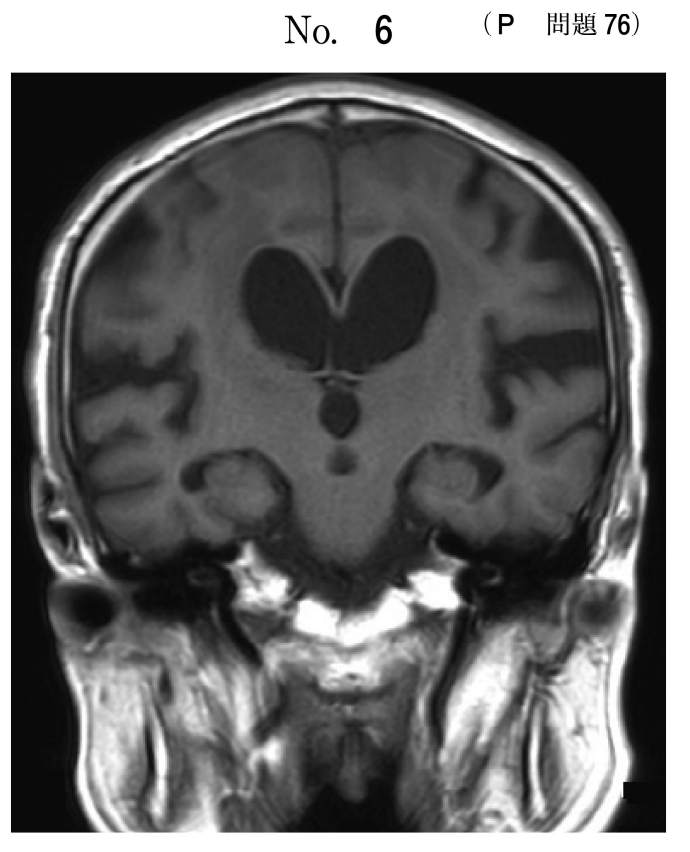

歩行障害がある患者の頭部MRIのT1強調冠状断像(別冊No.6)を別に示す。腰椎穿刺を行い髄液を排出させたところ、歩行障害が改善した。最も考えられるのはどれか。